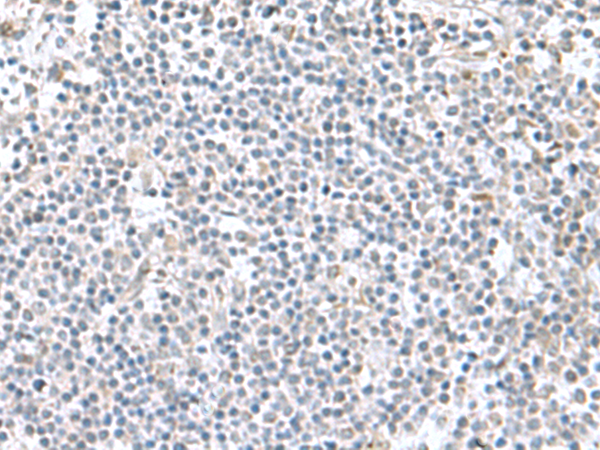

分类: 科研抗体货号: P10218别名: MSL1v2; C2orf67应用: IHC反应种属: Human, Mouse